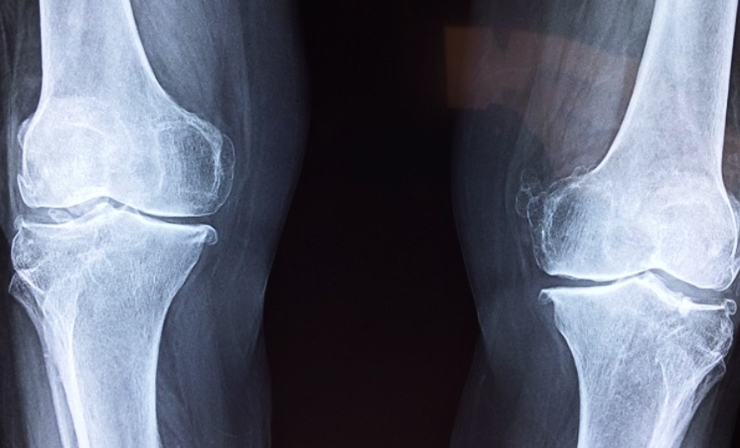

3. 계단을 오르거나 걸을 때 무릎이 아프다

퇴행성 관절염의 초기 신호 중 하나는 계단을 오르내릴 때 무릎이 뻐근하거나 통증이 느껴지는 것입니다. 관절을 움직일 때 연골이 마찰을 줄여야 하지만, 연골이 손상되면서 뼈끼리 부딪히는 느낌이 들 수 있습니다.

평지에서는 괜찮지만 계단을 오르거나 앉았다 일어날 때 통증이 심해진다면 관절염 초기 단계일 가능성이 높습니다.